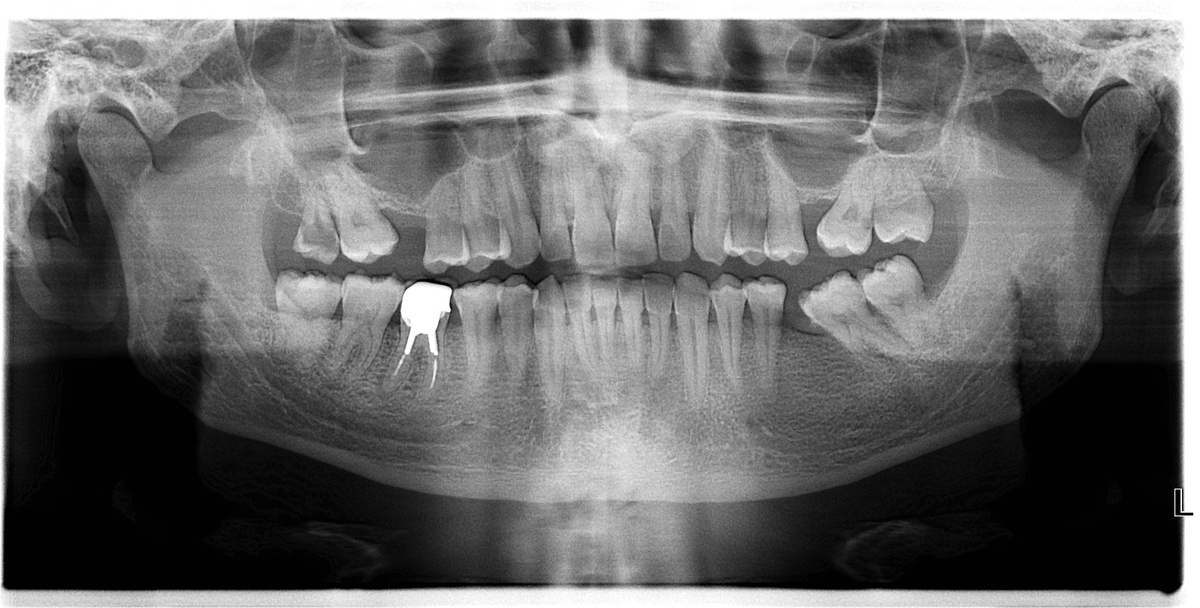

Снимок проводится до лечения.

Ортопантомограмма — это обзорный круговой снимок зубов, на котором представлена челюсть целиком, развернутая в плоскости. При помощи этого исследования можно диагностировать аномалии развития и расположения зубов и челюстей, кариес, в том числе под пломбой или коронкой, периодонтит, выявить стадию заболеваний пародонта, определить состояние костной ткани и др. Очень важно заранее сделать панорамный снимок, чтобы выяснить положение и состояние зубов мудрости.